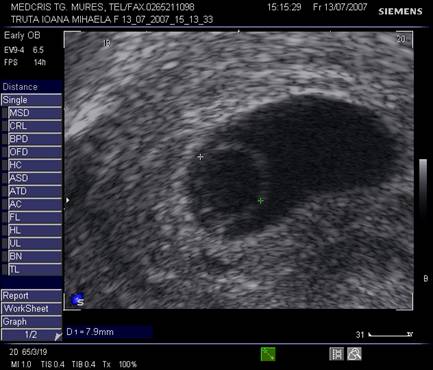

Oul clar este definit ca o sarcina anembrionata si fara sac Yolk (cca 1/3 din avorturile spontane) [10].

Incidenta anomaliilor cromozomiale este mai mare decat la avorturile cu embrion prezent, in special a trisomiilor. Ecografia transvaginala va indica un sac gestational gol, a carui marime este corespunzatoare relativ la durata amenoreei, eventual cu usor contur neregulat.

Pentru a nu face o eroare de diagnostic in prezenta unui sac gestational prea mic , posibil al unei sarcini incipiente, o reevaluare la o saptamana va fi necesara.

Fig. nr. 82 Ou clar la ecografia transvaginala